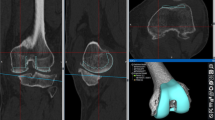

Verification of the tactile scanning procedure

The accuracy of the scanning procedure was verified by fitting the sampled point clouds of the femoral implant surface to the computer-aided design (CAD) files of the corresponding femoral components. Implant CAD surfaces and recorded point clouds were spatially aligned using best-fit alignment optimization of the 3D software Geomagic® Studio 2013 (3D Systems, Rock Hill, SC, USA). Reconstruction accuracy was evaluated based on the relative distance of a recorded sample point to the true implant surface. To ensure the algorithm’s function, this procedure was repeatedly performed for 21 right knees. The mean minimum and maximum deviations from the postoperatively sampled points to the respective implant surface were 0.27 mm and 1.89 mm, respectively. Concerning all patient cases, a mean distance error of 0.79 mm was determined, while the average root mean square error (RMSE) was 0.65 mm. An example of a fitted point cloud (red) to the implant surface is illustrated in Fig. 1.

The relevant surfaces of the knee joint were reconstructed from point clouds, which were obtained by means of tactile surface scanning that was manually performed by the surgeons. During each intraoperative measuring procedure, approximately 400–500 points on the anterior cortex, including the patellofemoral contact area, were sampled and recorded (Fig. 2a, b) for offline processing and evaluation. In the following section, the data processing, surface reconstruction, and parameter determination procedures are described in detail.

The data were imported in MATLAB (The MathWorks® Inc., Natick, MA, USA) and processed according to the following workflow: using the tactile scanner, the surgeons registered points of important anatomical landmarks for the establishment of the reference system and manually sampled the anterior femoral cortex intraoperatively by using the pointing device (Fig. 2a). The sampled point data were imported in MATLAB as a text file from which 3D location coordinates were retrieved to reconstruct the surface of the anterior cortex by triangulation from the intraoperatively sampled points. The space between the points was represented by linear interpolation. The surface was therefore generated as a polygon model where the triangles were represented by the nodes as their corners (Fig. 2b, c).

Workflow for the surface reconstruction of the femoral anterior cortex by means of the intraoperatively recorded point cloud. Using a commercially available navigation system (Precision Knee Navigation software v4.0, Stryker Orthopaedics, Mahwah, NJ, USA) with the tactile scanner (a), the anterior cortex was sampled with emphasis on the trochlear groove before and after total knee arthroplasty. The recorded point clouds (b) served as the basis for the surface reconstruction using an in-house code (c)